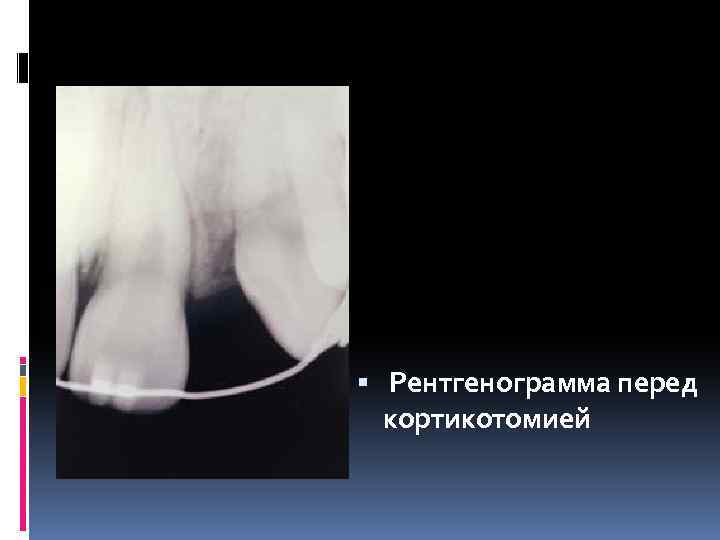

Рентгенограмма перед кортикотомией Рентгенограмма перед кортикотомией

Рассмотрим пример коррекции пространства на примере пациента мужского пола европеоидной расы, возраст 19 Рассмотрим пример коррекции пространства на примере пациента мужского пола европеоидной расы, возраст 19 лет

У него изначально отсутствовал зуб 1. 1 У него изначально отсутствовал зуб 1. 1

Лечение в данном случае заключалось в увеличении пространства между зубами, которое даст возможность Лечение в данном случае заключалось в увеличении пространства между зубами, которое даст возможность поставить имплантат на месте зуба 1. 1